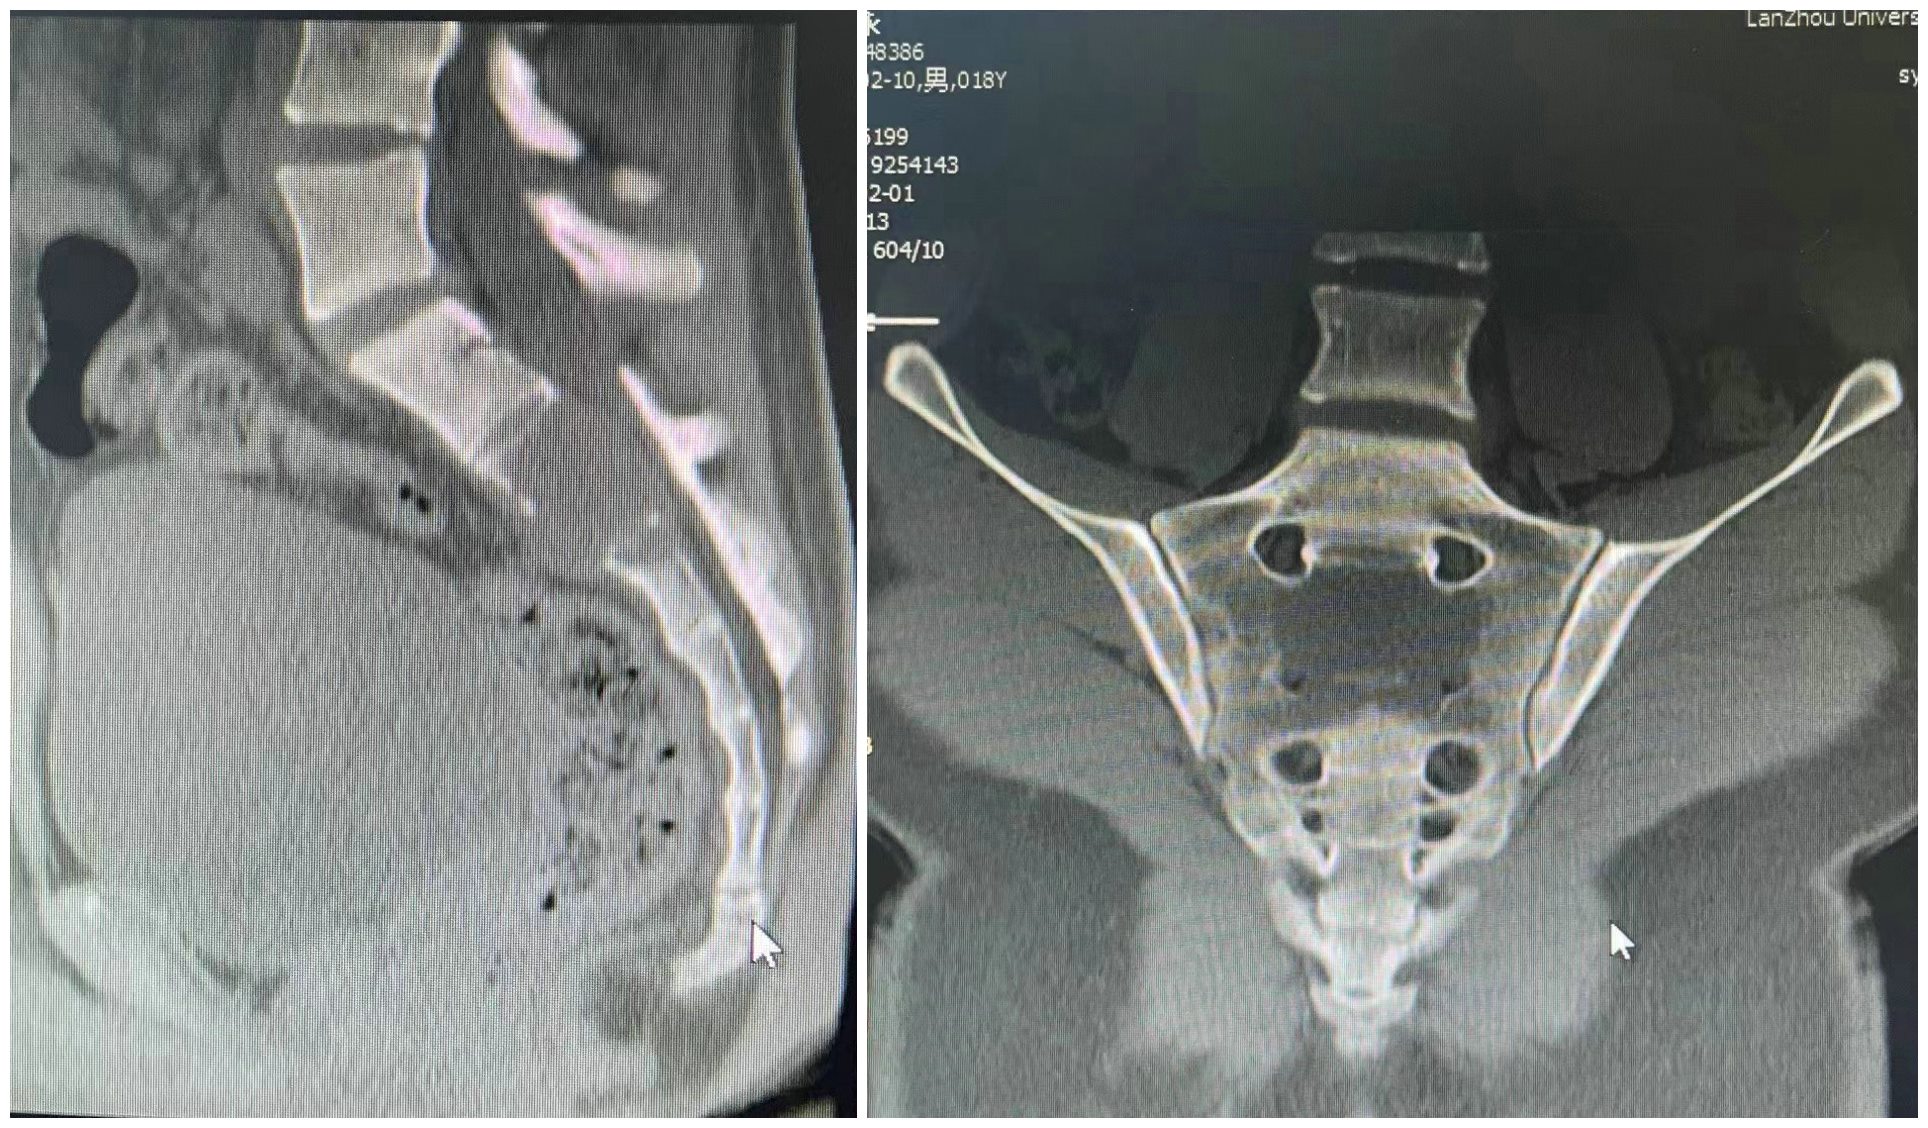

患者为18岁男性,因渐进性加重的骶部疼痛伴下肢无力半年收住入院(图片1、2)。入院后,完善相关检查,穿刺活检诊断为骶骨2、3巨细胞瘤,ki67达到60%,属于Campanacci3级(图片3)。影像显示瘤体侵袭骶骨2、3椎体,突破骶骨前方,向后突入椎管,压迫骶神经(图片1、2)。

图2 术前CT